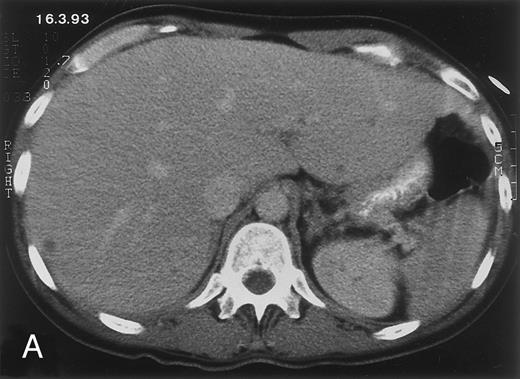

Radiologic evolution in patient A. (A) Postcontrast abdominal CT scan on March 16, 1993 shows multiple small hypodense areas in all segments of the liver, suggestive of hepatic candidiasis. Seven days previously, the patient had recovered from severe neutropenia after the first cycle of chemotherapy for AML. (B) On April 23, 6 days after the neutrophil count had dropped below 500/μL in the second cycle of chemotherapy, there is no evidence of focal lesions on postcontrast CT scan. (C) On June 18, when neutrophils were normalized for 46 days, CT scan again shows multiple small abscesses.